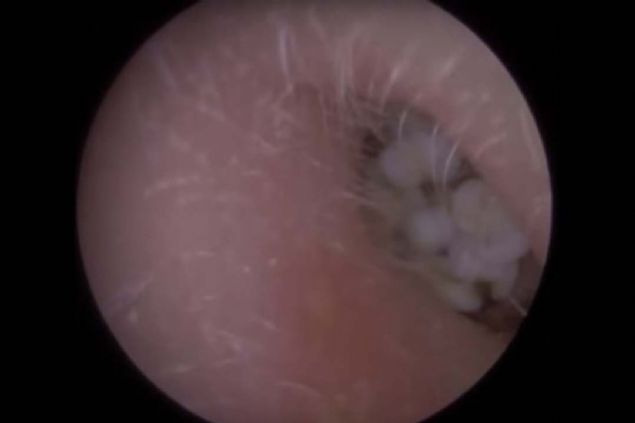

Kolundaki yaranın içinden çıkanlara kimse inanamadı!

Kolunda yara çıkan genç kadın sivilce zannedip önemsemedi ancak gerçek doktora gidince ortaya çıktı.

Yaranın içinden çıkan tropikal bölgede yaşayan ve larvalarını deri altına bırakan botfly cinsi sinekti.

Kolunda yara çıkan genç kadın sivilce zannedip önemsemedi ancak gerçek doktora gidince ortaya çıktı.

İşte o anlar...